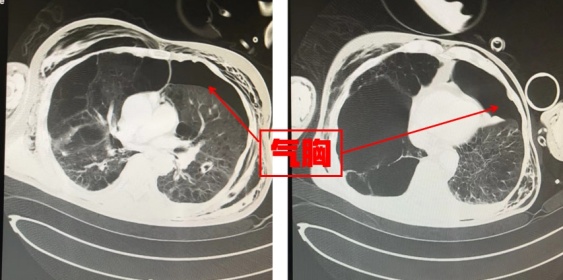

会诊后,同济医院胸外科予以急诊行“左侧胸腔闭式引流”;急诊创伤救治中心行“右侧胫骨外固定+清创术”;普通外科行“开腹探查+全脾切除术”,考虑到患者病情尚不稳定,术后转入重症医学科继续治疗。

唯一令人头疼的事情就是老周的肺部情况,虽然呼吸机支持力度已经逐渐下调,但此次的肺损伤对于本就严重功能减退的肺部而言,无疑是雪上加霜,使得恢复之路更加艰难而漫长。考虑到老周肺部情况,重症医学科经过全科讨论,对其进行了“气管切开术”,并联系康复医学中心的医师为老周开始了一系列的肺康复治疗。经过近一个月的治疗,老周逐渐清醒,并顺利脱离呼吸机,并且转出监护室继续康复治疗。